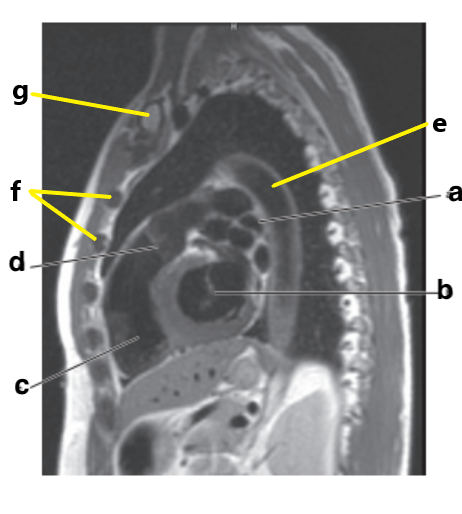

Which letter is the ascending aorta ?

f

What is letter a ?

Ascending aorta

Aortic Arch

What is letter d ?

Right ventricle

Which letter is the descending thoracic aorta ?

e

What is letter g ?

Descending aorta

Descending thoracic aorta

What is letter e ?

Thoracic vertebra

What is letter f ?

Sternum